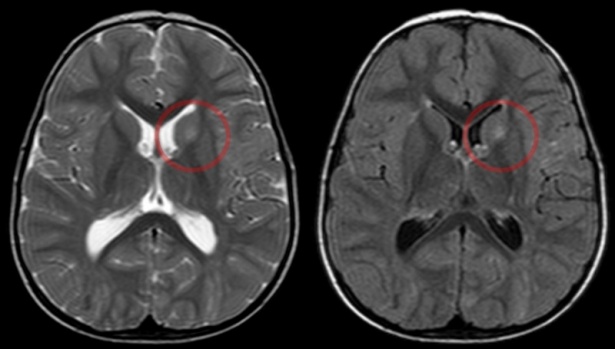

Лекарите често откриват хамартоми по време на образна диагностика поради други оплаквания от друго заболяване. Пациентите обикновено се нуждаят от допълнителни образни изследвания, за да потвърдят диагнозата.

Изображение: Hellerhoff, CC BY-SA 4.0, via Wikimedia Commons

Образните изследвания, от които може да се нуждаят пациентите, включват:

За потвърждаване понякога може да се наложи извършването на биопсия, ако лекарят не е сигурен, че образуванието не е злокачествено. Отстранява се част от тъканта, която се изпраща в лаборатория за хистологичен анализ.

Заглавно изображение: Hellerhoff, CC BY-SA 3.0, via Wikimedia Commons